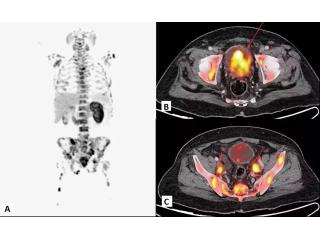

As 2026 marks a transformative era for oncology in Mumbai, the focus has shifted toward identifying the tumor microenvironment for superior diagnostic accuracy. Picture This leads this advancement by offering the highly specialized fapi pet ct, a breakthrough for patients whose conditions may not be clearly visible on conventional scans. Unlike traditional glucose-based imaging, the fapi pet ct scan targets fibroblast activation proteins, providing exceptional contrast for pancreatic, gastric, and various soft-tissue malignancies. This "Humanized" diagnostic approach is particularly beneficial for diabetic patients, as it requires no fasting or blood sugar monitoring, ensuring a much more comfortable experience. Located in the heart of Mumbai’s medical district, our facility combines cutting-edge 3T technology with subspecialty expertise to deliver the clarity required for life-saving treatment plans. Whether you are seeking a first-time diagnosis or a precise second opinion, our team is dedicated to providing world-class results. Contact Picture This today to schedule your advanced molecular evaluation.